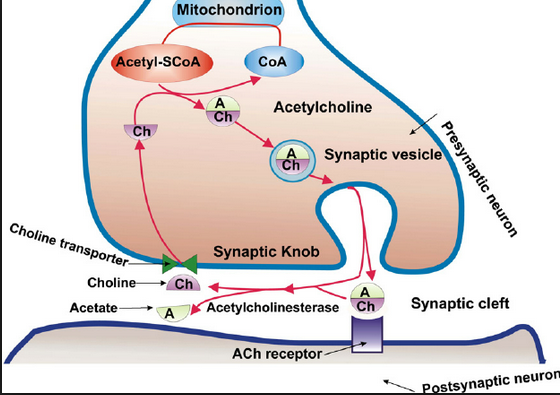

and the LINK to the bio-molecular communications molecule ……ace –> acetylcholine

Acetylcholine – Wikipedia, the free encyclopedia

https://en.wikipedia.org/wiki/Acetylcholine

Wikipedia

Acetylcholine is an organic chemical that functions in the brain and body of many types of animals, including humans, as a neurotransmitter—a chemical …

History · Function · Synthesis and degradation · Receptors

Acetylcholine Neurotransmission (Section 1, Chapter 11 …

neuroscience.uth.tmc.edu › Table of Contents

11.1 Introduction. Acetylcholine, the first neurotransmitter discovered, was originally described as “vagus stuff” by Otto Loewi because of its ability to mimic the …

Acetylcholine – Neuroscience – NCBI Bookshelf

www.ncbi.nlm.nih.gov › … › Bookshelf

National Center for Biotechnology Information

by D Purves – 2001

Acetylcholine is the neurotransmitter at neuromuscular junctions, at synapses in the ganglia of the visceral motor system, and at a variety of sites within the …

Choline transporter —> newspaper messages via –> Cho + line –> Mr. Cho an English major and Virginia tech and his line(s) …. choline messages

Acetylcholine – Wikipedia, the free encyclopedia

https://en.wikipedia.org/wiki/Acetylcholine

Wikipedia

Acetylcholine is an organic chemical that functions in the brain and body of many types of ….. The enzyme acetylcholinesterase converts acetylcholine into the inactive metabolites choline andacetate. This enzyme is abundant in the synaptic …

acetylcholinesterase converts acetylcholine into the inactive metabolites choline and acetate.

the inactive metabolites choline and acetate.

the inactive metabolites choline and acetate.

the inactive metabolites ……………….acetate.

the inactive metabolites ……………….ace …. tate.